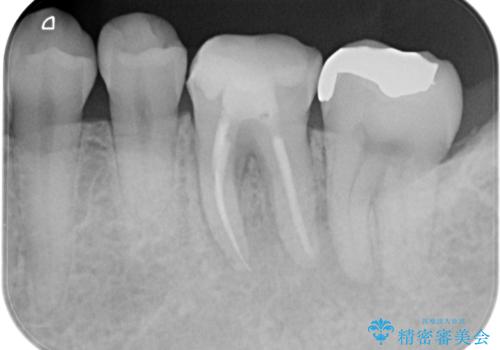

根管治療から被せ物の治療

- 噛んだ時の痛みを主訴に当院受診されました。

根管治療を行なったのち、症状改善を認めオールセラミッククラウンにて修復治療を行なっております。

┌7は今回の治療後打診(-)、正常歯髄へ診断のもと経過観察を行なっております。